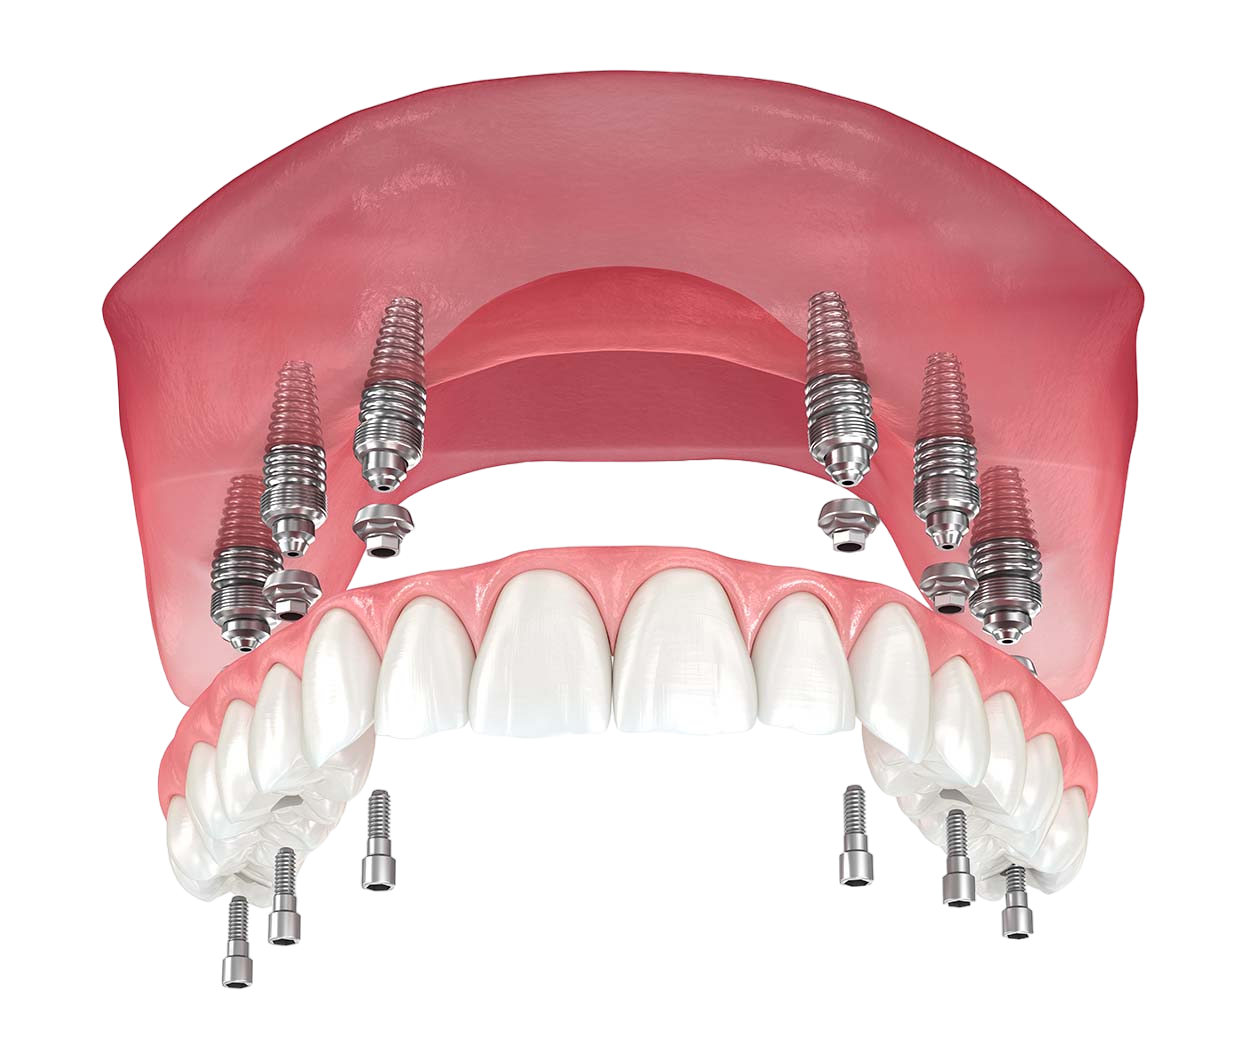

Procedure Techniques of All-On-6 Dental Implants

- Placement of Implant – 6 best quality titanium-made implants are settled at tactically measured angles for supreme stability